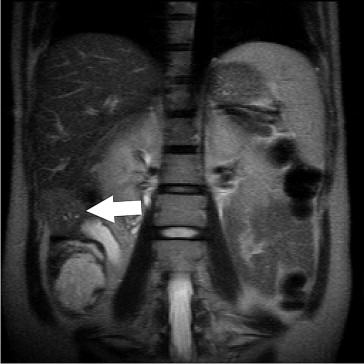

A 30-year-old woman presented with her first pregnancy at 25 weeks gestation. She received routine pregnancy check-up and abdominal ultrasonography incidentally revealed a tumor mass over the right lobe of the liver. She was seronegative for both hepatitis B and C viruses. The maternal serum α-fetoprotein was 305 ng/mL (normal range: < 12 ng/mL). Magnetic resonance imaging showed a 42-mm hepatic mass with an irregular margin at the inferior part of segment (S)6 (Fig. 1). We performed subsegmentectomy of S6 and cholecystectomy at 26 weeks gestation. No cirrhosis was found during the operation. The pathology reported an HCC, which was poorly differentiated, with a free resection margin. The patient recovered uneventfully and was discharged home on postoperative day 8.

Magnetic resonance imaging showed a 42-mm hepatic mass in the inferior part of ...

Figure 1.

Magnetic resonance imaging showed a 42-mm hepatic mass in the inferior part of segment 6, with a slightly high signal on no-fat-saturated T2-weighted imaging (arrow).